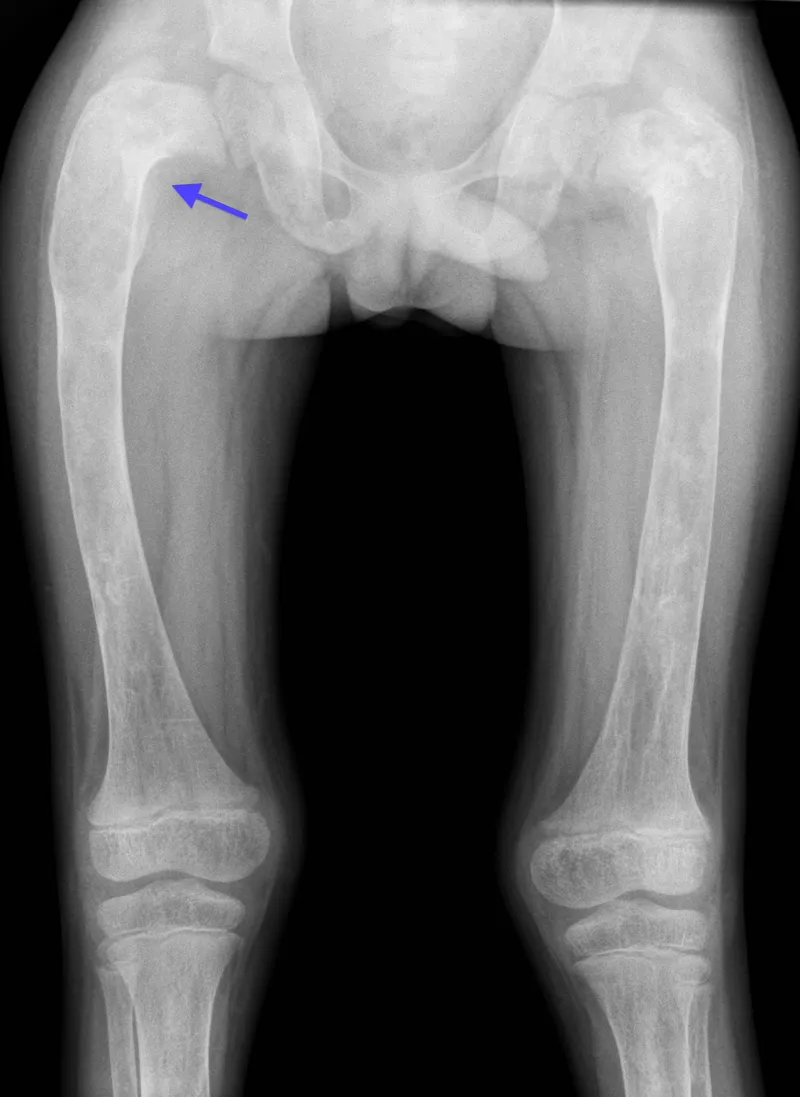

- X-ray: "Ground glass" opacity, "Shepherd's crook" deformity (femur).

- Fibrous dysplasia: Ground-glass matrix, Shepherd's crook deformity, McCune-Albright syndrome.